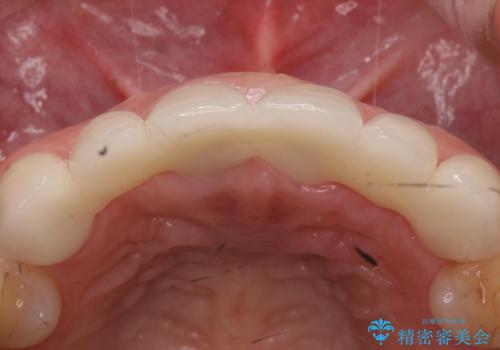

- 入れ歯での生活がストレスで他のものに変えたいとのことで来院された患者様です。

根の状態も良くなかったため、根管治療から行うこととなりました。

左上2番の歯は歯根が割れていたため抜歯し、入れ歯をブリッジに変えていきます。